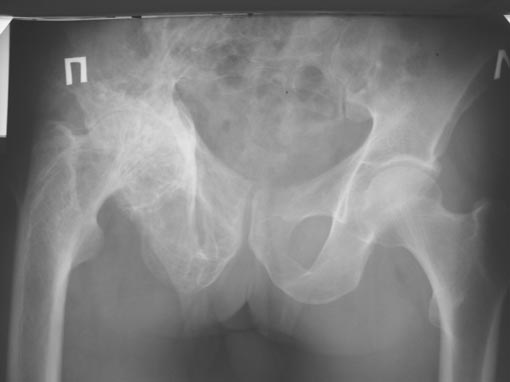

Больной 55 лет, страдает болезнью Педжета.

Сформировалась грубая сгибательно-приводящая контрактура, ортопедическое укорочение 6см, движения в суставе - минимальные. Вызывает сомнение стабильность фиксации вертлужного компонента.